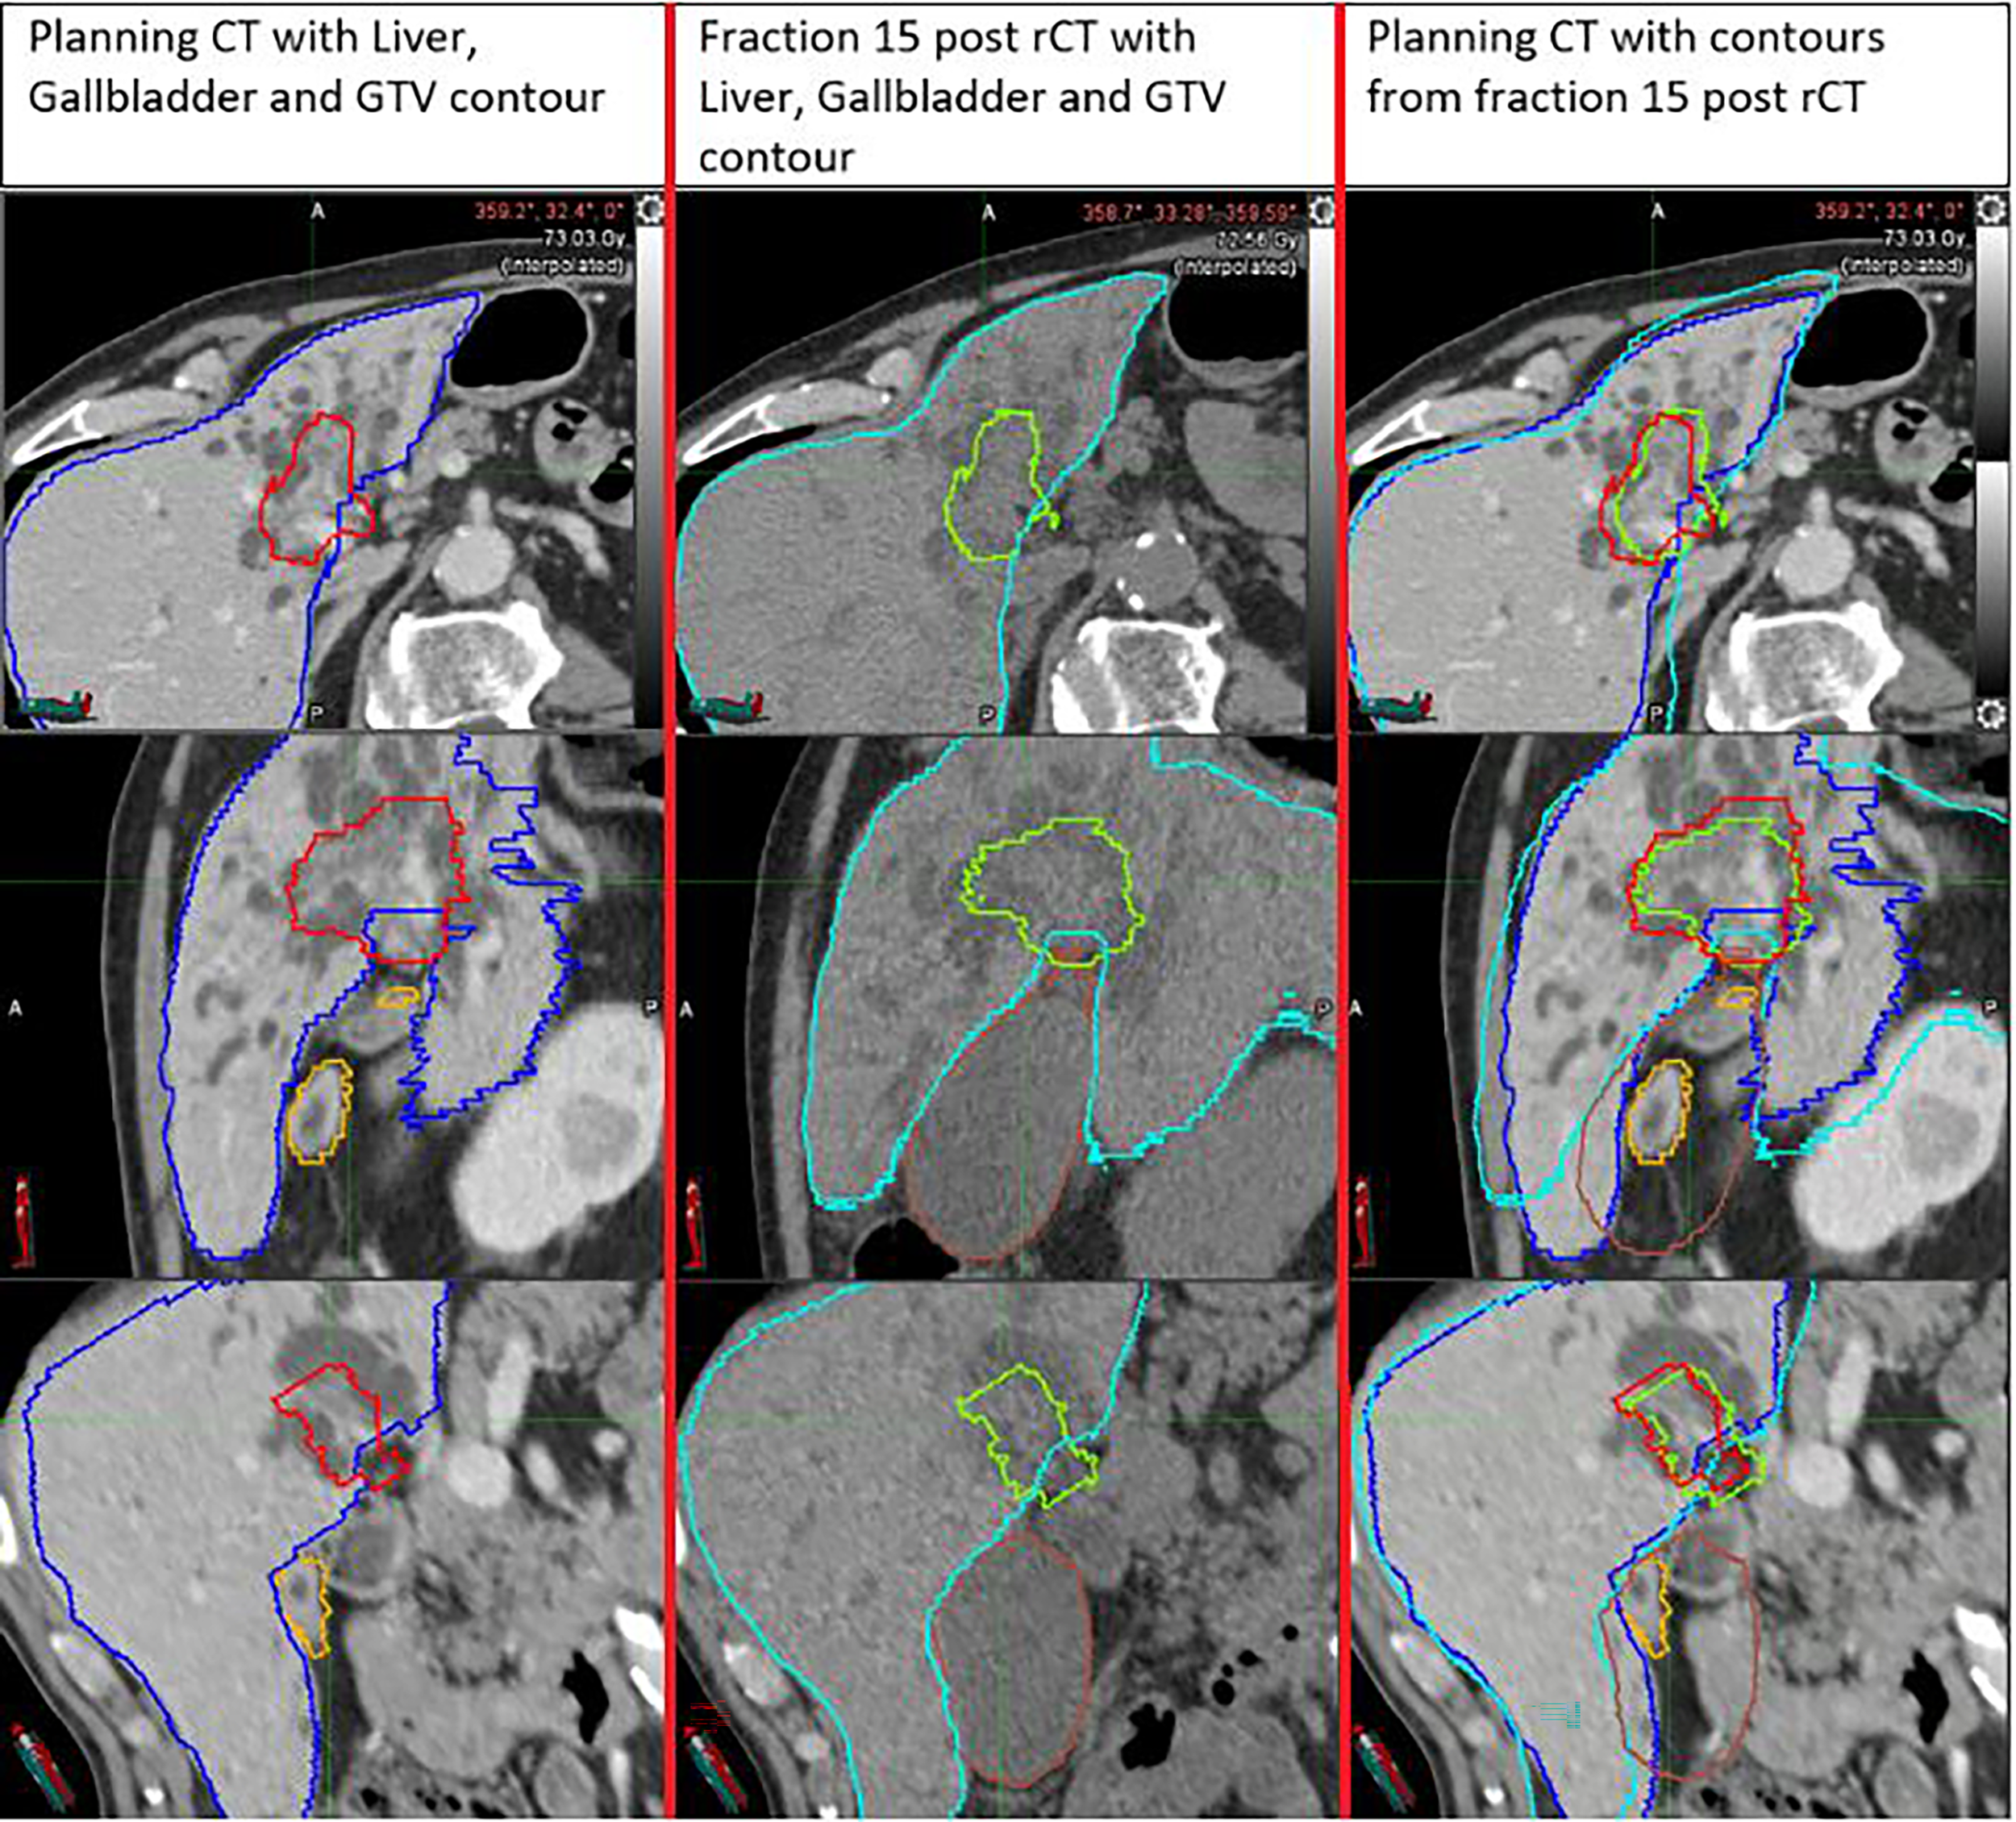

Two of the greatest coverage losses were observed for patient 5 in the last treatment fraction (18.0% in pre-rCT and 17.7% in post-rCT). Inspection of the scans showed that these target losses were related to significant increases in the gallbladder volume during treatment (7.6 cc in the pCT vs. 61.3 in the pre-rCT and 79.8 cc in the post-rCT). Due to this effect, the fiducials were pushed further away from the target than in planning, causing a partial mismatch between the rCT PTV and the high dose volume delivered (Figure 3).

Figure 3

Example of a large PTV coverage loss (17.7%) in the post-rCT of the last fraction of patient 5, compared to pCT. The increased gallbladder volume pushed the fiducial away from the target, leading to less efficient tracking and considerable underdosage of the target.